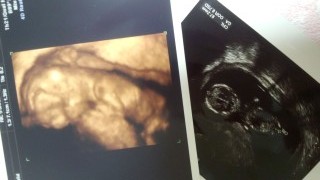

4Dです!こんなによく分かるエコー写真に感動しました!旦那もとてもびっくりしてました!愛おしいです!!

初4Dでは、ちっちゃな左肩も見えて、よりいとおしくなりました♪